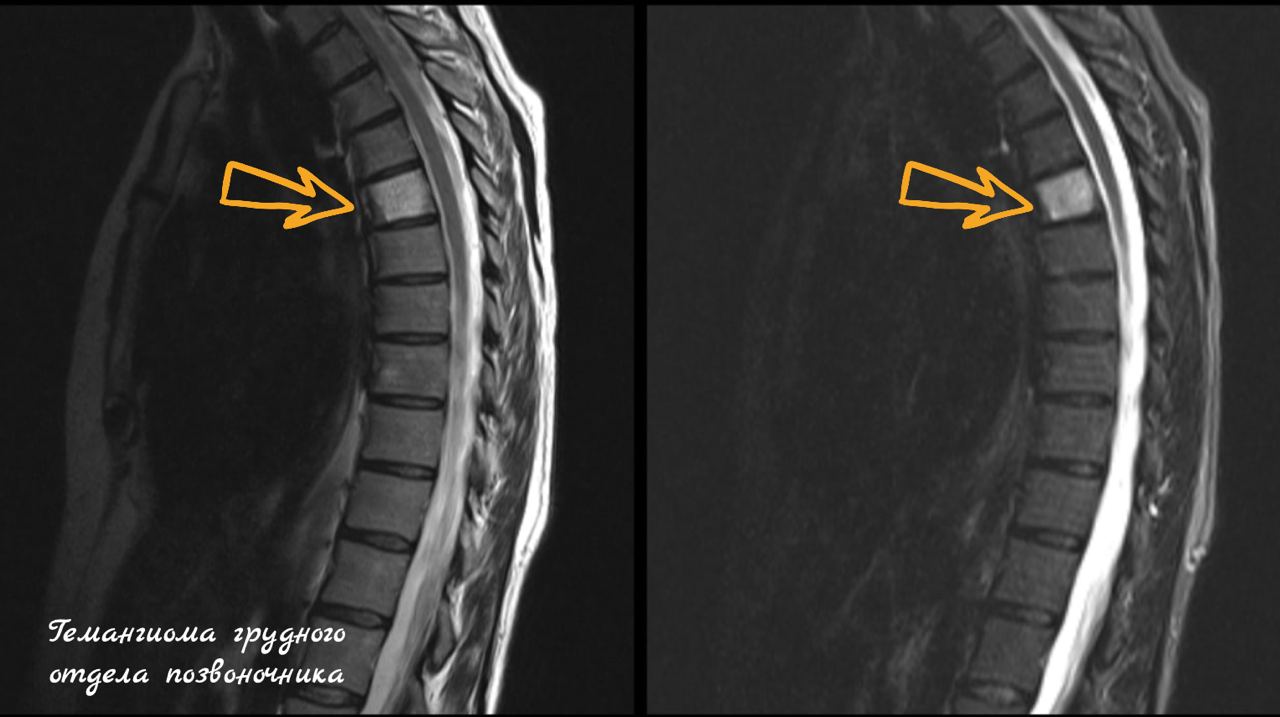

- Магнитно-резонансная томография (МРТ) — «золотой стандарт». Она безопасна (нет облучения) и идеально показывает саму гемангиому, её тип, а также сдавление спинного мозга и нервов.

- Компьютерная томография (КТ) — лучше всего показывает изменения в костной структуре позвонка, «клубничный» узор и возможное разрушение кости.

- В грудном и поясничном отделах позвоночника.

- Типичные (99% случаев): содержат много жира, стабильны, не растут. На снимках имеют характерный «клубничный» или «полосатый» рисунок. Не требуют лечения.

- Атипичные: содержат больше сосудов, менее жирные. Нуждаются в наблюдении, так как их сложнее отличить от других образований.